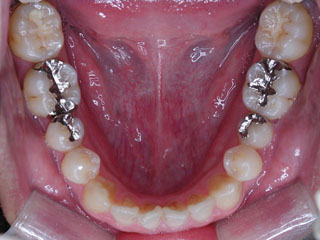

上顎前歯の前突が見られます。下の歯には中程度の叢生と口唇前突感がみられました。分析結果では、2級1類と呼ばれるタイプの不正咬合でした。上顎の左右第一小臼歯を抜歯してマルチブラケット治療を行いました。

使用した主な装置名:TPB、HG、マルチブラケット装置

抜歯/非抜歯および抜歯部位:抜歯(上顎左右第一小臼歯)

治療期間:動的処置2年6か月、経過観察3年6ヶ月